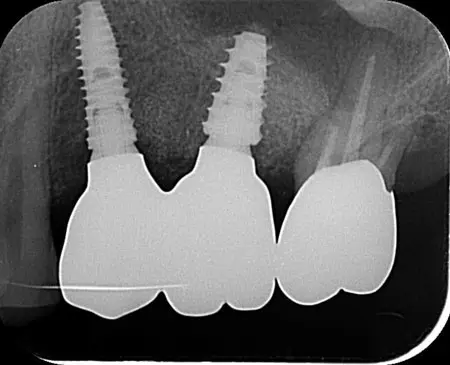

2024.08.1740代男性「虫歯により抜歯になった」サージカルガイドを使用したインプラントの症例【セカンドオピニオン】